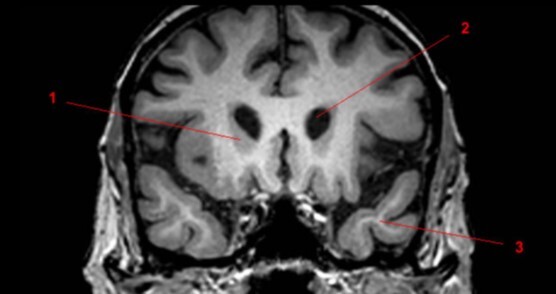

17

Label 1-3

A

1-Lt Optic nerve

2-Optic chiasm

3-Rt Optic tract